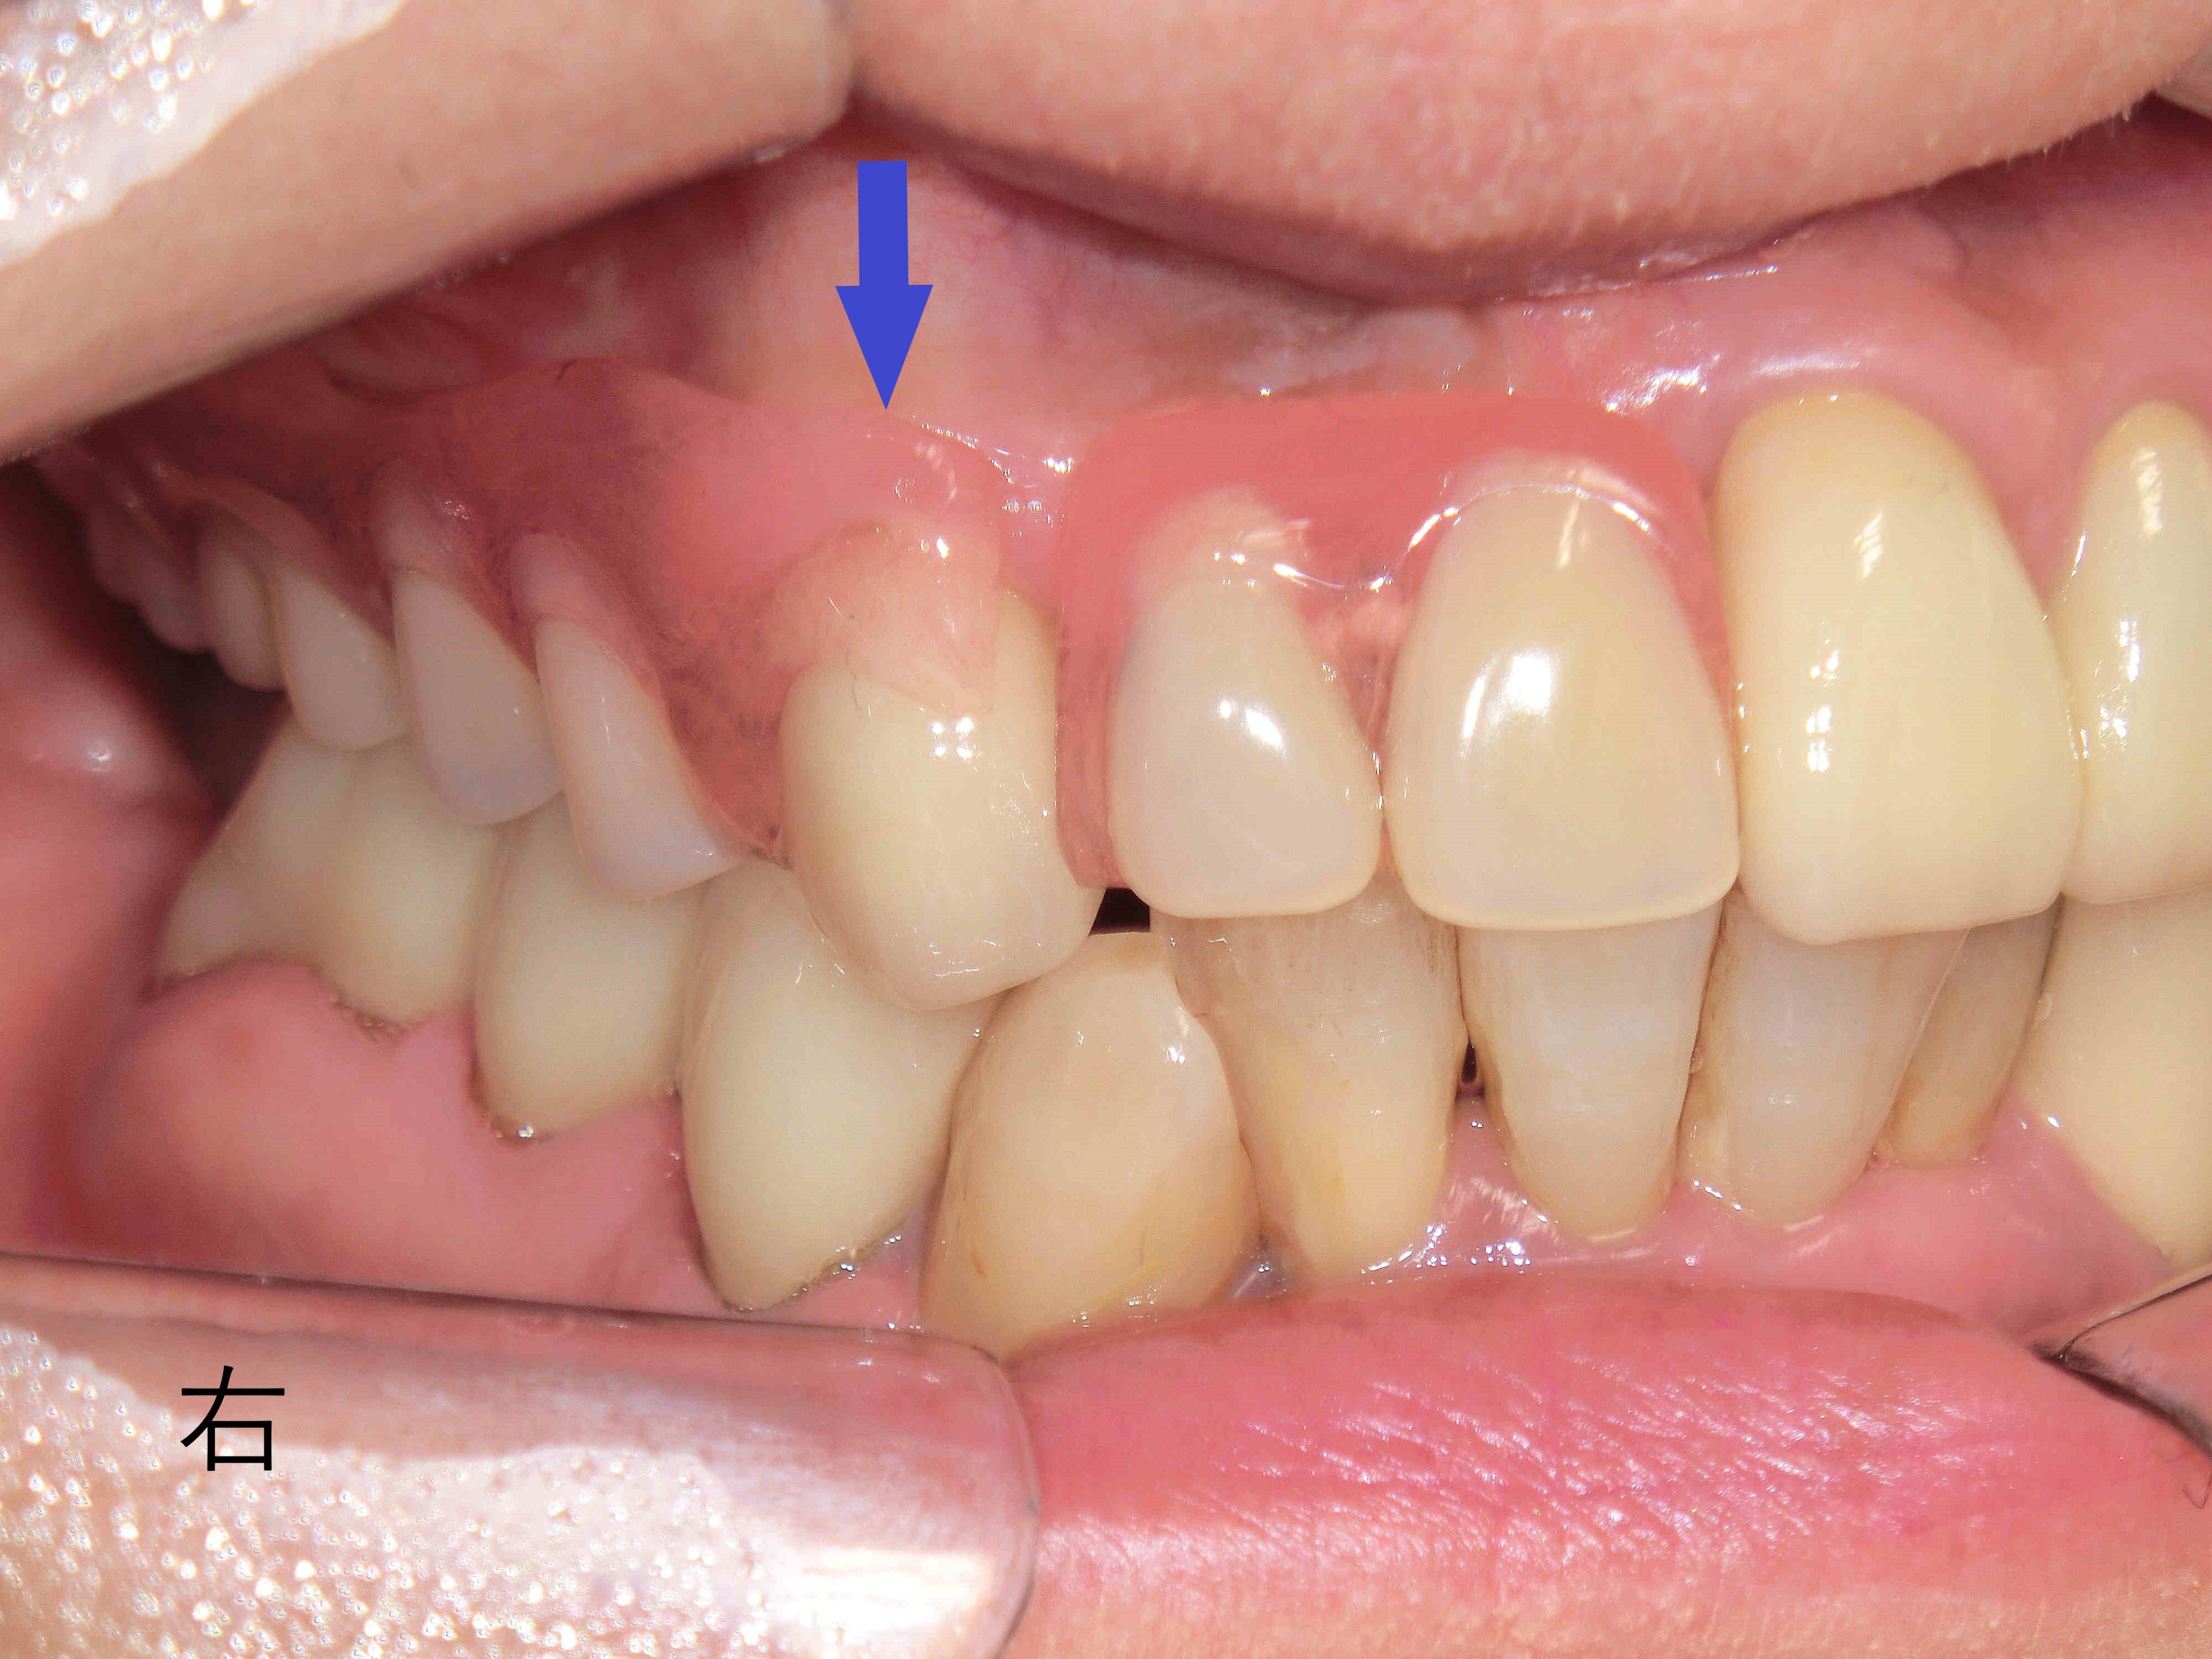

上下顎に保険適用の義歯を装着した状態を正面から撮影したもので、上顎には前歯しか残存歯がなく、その前歯に義歯を固定するため、金属製のバネ(クラスプ)を装着する必要がありました(青色矢印)。

前歯部に金属のバネがかかっているため、審美性が損なわれているのがわかります。

この患者様は中等度以上の歯周病に罹患しており、抜歯を含む全顎的な治療が必要となったため、義歯による補綴治療が選択されました。